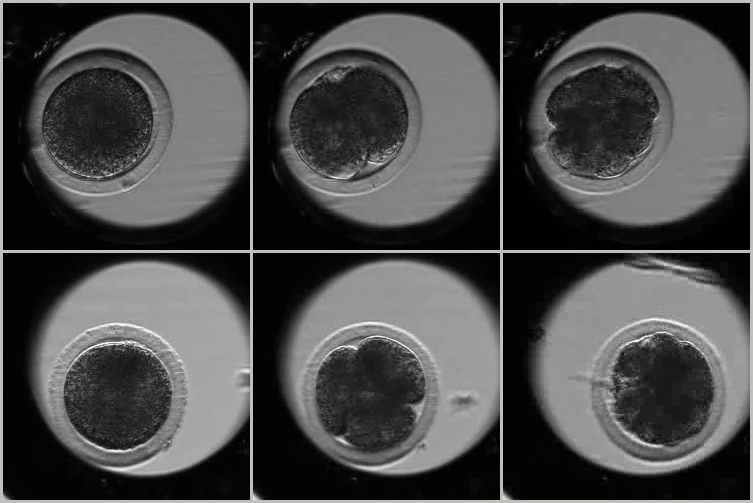

Fig. 2: Two sample videos of IVF bovine embryos, with three images taken at distant time instants (top row: an example from class transferable; bottom row: an example from class non transferable). The bovine embryo (dark grey), surrounded by the zona pellucida, is located in a micro-well (light grey) within the Petri dish (black). The embryo occupies a small part of the image.

We formulate this problem as a two-class supervised classification one: the embryo is transferable (T class) or not transferable (NT class). This problem is challenging for three main reasons: 1) tricky embryo appearance and motion, 2) class ambiguity, and 3) small amount of annotated data. First, as illustrated in Fig.2, the microscopy videos display little contrast, involve a lot of noise and complex motion with transparency effects. The diverse embryos studied often exhibit poorly discriminating appearance between classes (see Fig.2 again), while the videos show complex morphological and temporal processes. Second, the intra-class variability is high, in the sense that the trajectories of the embryo development may substantially vary within a given class. Conversely, the inter-class distance is low. Indeed, observed development of two embryos from the two different classes may be fairly similar for the four first days. Third, because labeling is costly, there is only a limited database of videos labeled transferable or not transferable.